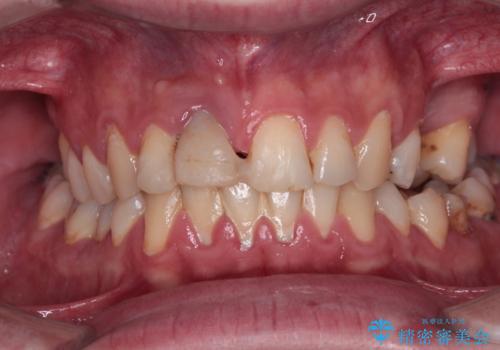

度重なる脱離により、表側の炎症が非常に強くなっており、歯を支える骨が失われている状態でした。

そのため、現在の位置よりも歯と歯肉の位置が退縮する方向に移動する可能性があり、前歯2本の歯肉位置が大きくずれることとなるため、本人との相談のうえ、天然歯が萌えているような歯肉状態とはならないものの、2本の段差が少ない状態にて治療を終えることとなりました。